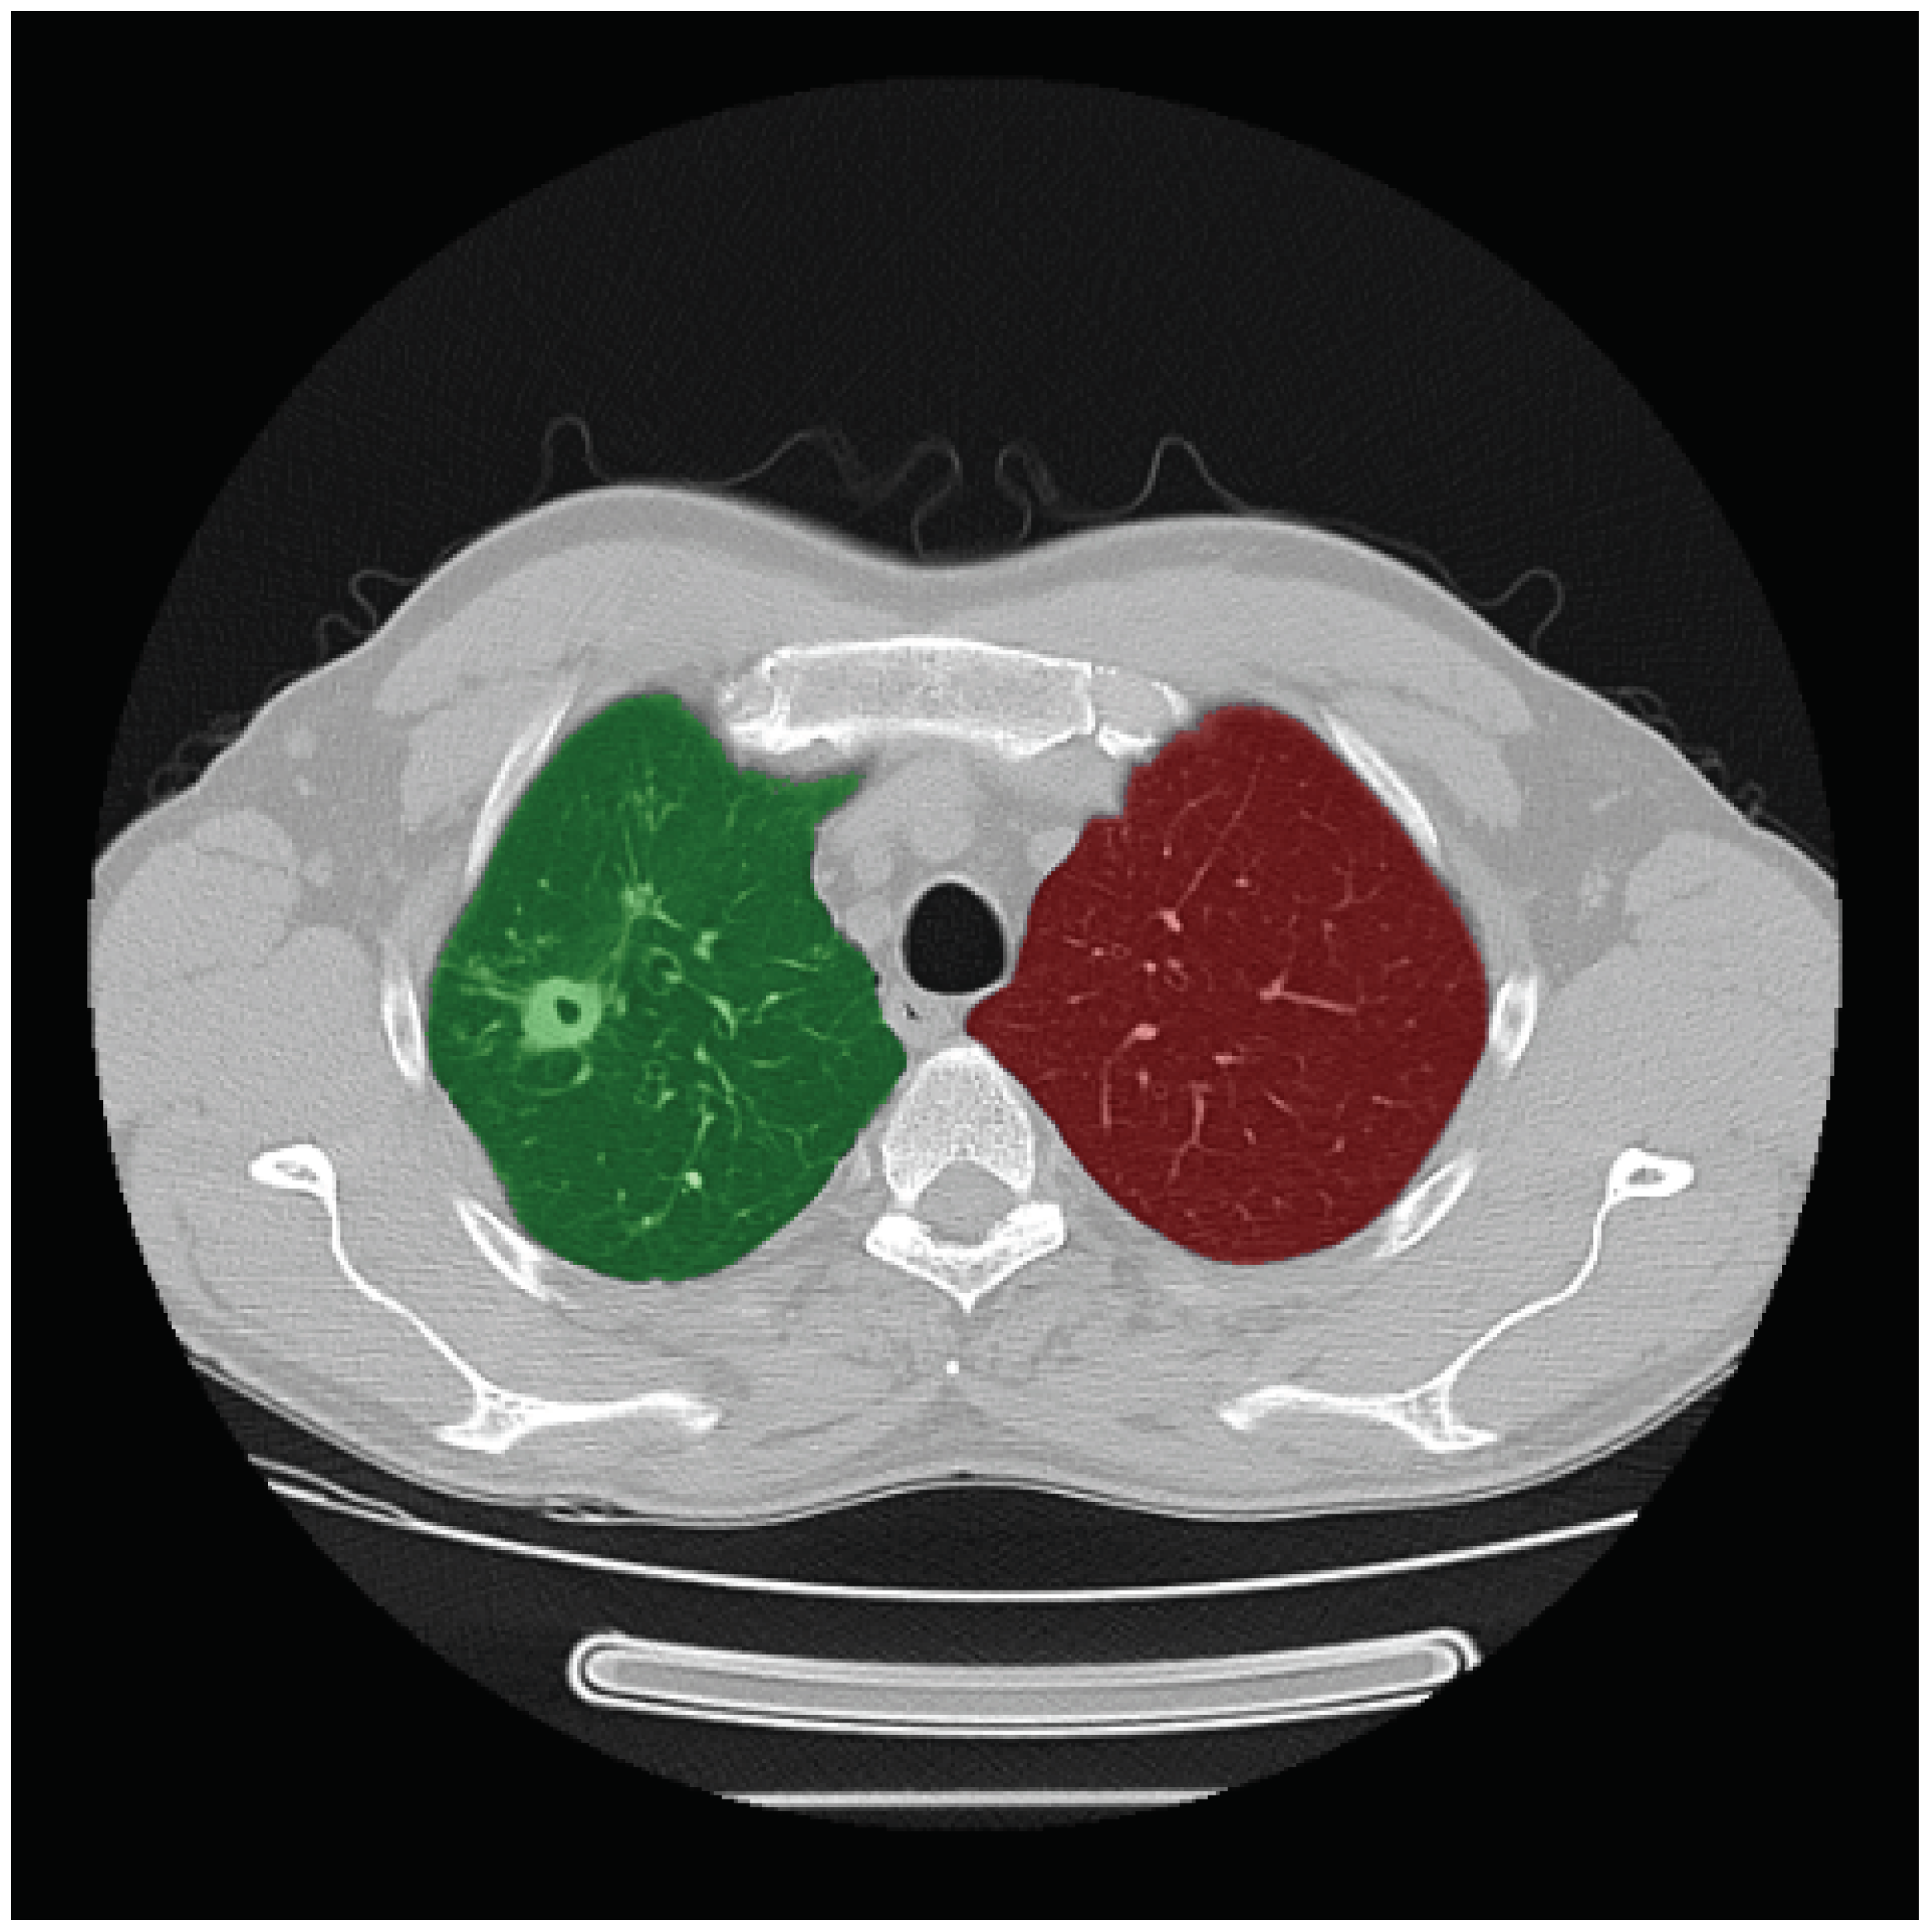

- Dicente Cid, Y.; Jiménez del Toro, O.A.; Depeursinge, A.; Müller, H. Efficient and fully automatic segmentation of the lungs in CT volumes. In Proceedings of the VISCERAL Anatomy Grand Challenge at the 2015 IEEE ISBI, CEUR-WS. New York, NY, USA, 16 April 2015; Goksel, O., Jiménez del Toro, O.A., Foncubierta-Rodríguez, A., Müller, H., Eds.; CEUR Workshop Proceedings. pp. 31–35. [Google Scholar]